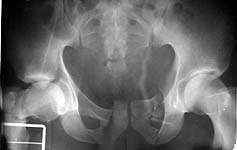

A 23 y.o. male after a car accident transferred to us from elsewhere at 4th day since the injury. He has the pelvic ring lesion including fracture of the left acetabulum, and ipsilateral femoral neck and shaft fractures - images attached. The shaft fracture is open grade II, debrided at the initial hospital - no sign of infection to date.

Reduction is going to be critical to success in this young man, because his fracture looks like it goes pretty high in his dome. Do you have Judet views and a CT scan you can show us?

I would also repair his pubic rami fractures. But there are lots of people in the US who think that's a bunch of hooey. You're going to have to reduce his right ramus fracture as part of your acetabular fracture reduction, I think. It looks like it needs to be rolloed forward and laterally. The left sided rami have been pushed inard - you'll need to draw them out to fix them. I can't tell if his superior and inferior rami are separate on these views. There may be a bridge of bone connecting them, but I can't tell if it's solid or not. If they are separate, then you'll need to approach him from front and back to be able to control all the parts of his T shaped fracture.

OK, we just fixed all fractures as the patient shows no infection signs. Posterior column was perQ (nice abbreviation) fixed by a screw and a wire, rami - by screws. Then closed locked nailing was performed (i placed a single screw at the upper level - is it commonly acceptable?) and "miss a nail" three cancellous screws to the neck (at the moment we have no more available implants suitable for this lesion like gamma nail etc, so the choice was easy :-). The external fixator left in place as a "local sceletal traction" for a couple of weeks. Acetabular, femoral shaft and neck images attached.